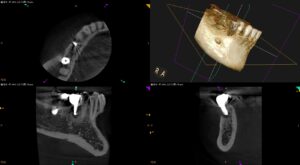

他院でImplantの隣の歯が折れていると言われたが, なるべくは自分の歯を保存したい…〜#29 Intentional Replantation

紹介患者さんの治療。 主訴は、 他院でImplantの隣の歯が折れていると言われたが, なるべくは自分の歯を保存したい… である。 Pre-op Endo Test(2026.2.2) #29のMBに5mmの歯周ポケット … 続きを読む 他院でImplantの隣の歯が折れていると言われたが, なるべくは自分の歯を保存したい…〜#29 Intentional Replantation